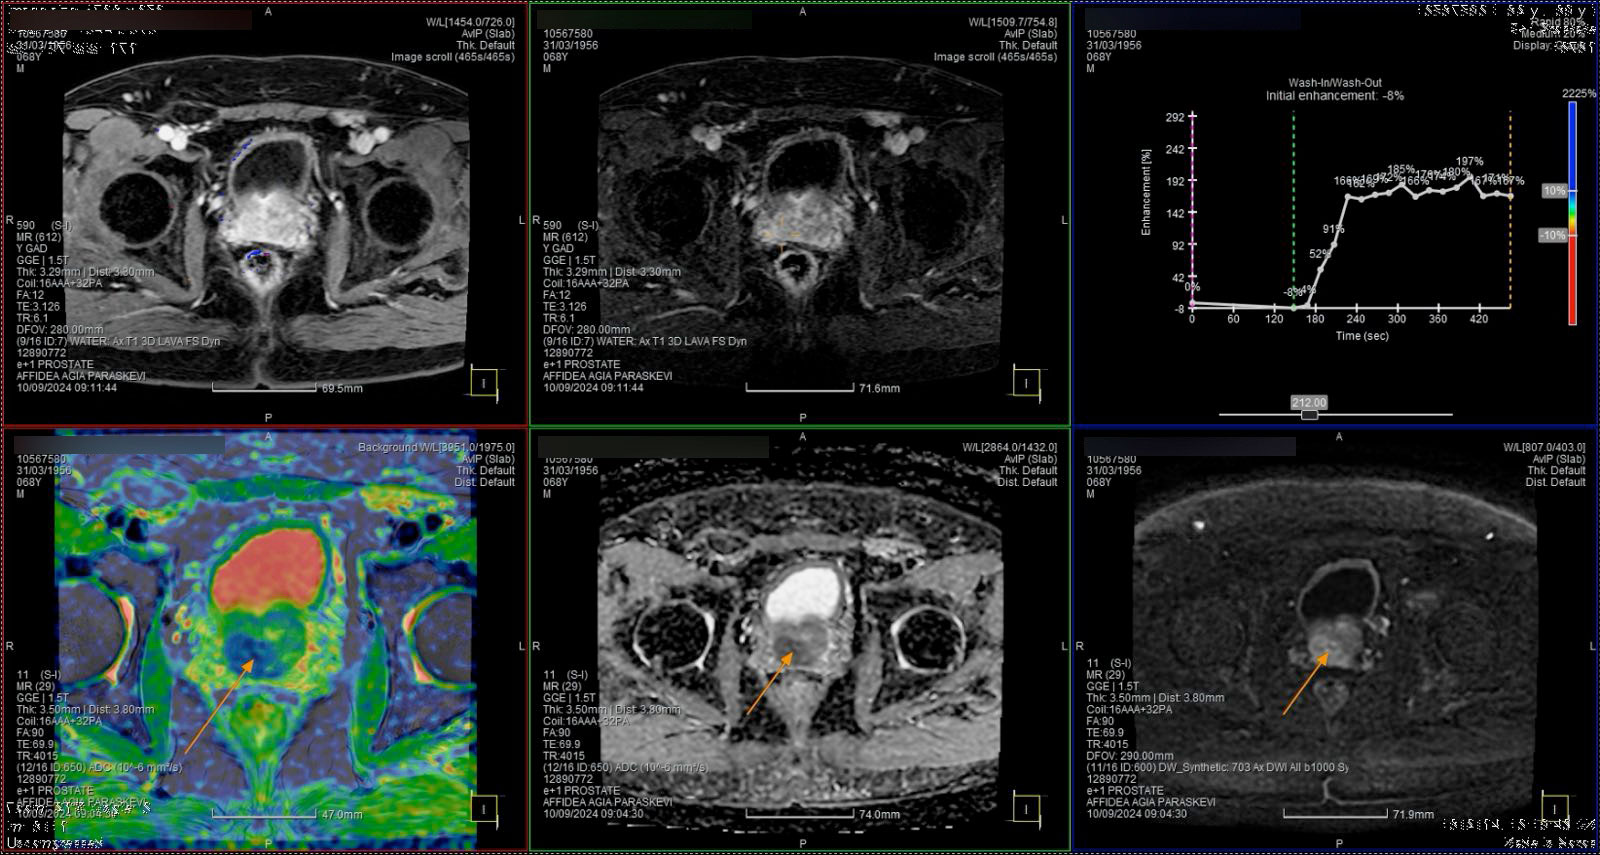

Στη περίπτωση που ο γιατρός εντοπίσει κάποια ένδειξη που θεωρεί ότι χρειάζεται περαιτέρω διερεύνηση, θα καθοδηγήσει τον ασθενή να υποβληθεί σε πολυπαραμετρική μαγνητική τομογραφία (MRI) του προστάτη, προκειμένου να έχει καλύτερη εικόνα της περιοχής.

Χρησιμοποιώντας μια ειδική κλίμακα ταξινόμησης (Prostate Imaging-Reporting and Data System – PI‑RADS) με βάση τα ευρήματα της MRI, ο Ουρολόγος θα αποφασίσει εάν ο ασθενής χρειάζεται να υποβληθεί σε βιοψία.

Αναφορά του συστήματος Biopsee όπου φαίνονται οι στοχευμένες βιοψίες στις βλάβες (δε) & (αρ) που μας εδειξη η Πολυπαραμετρικη MRI προστάτη , όπως και κάποιες στοχευμένες άμφω.